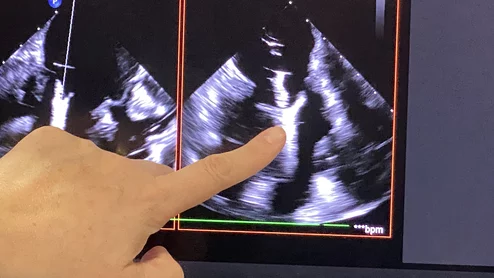

Thumbnail